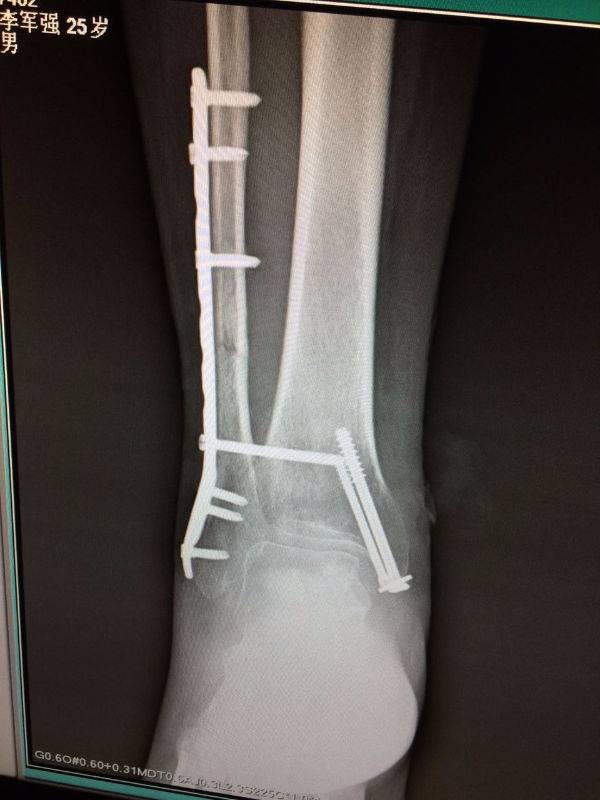

手术非常好,顺便请教一下。患者.男,25岁,右腓骨下段及内踝骨折,切开复位内固定术后120天,外踝部钢板外露,半月前行扩创缝合,目前仍未完全愈合,伴少量渗出,踝关节功能僵硬。请教治疗方案。谢谢

mmexport1496478281296.jpg

mmexport1496478334909.jpg

mmexport1496478329835.jpg

mmexport1496478319278.jpg